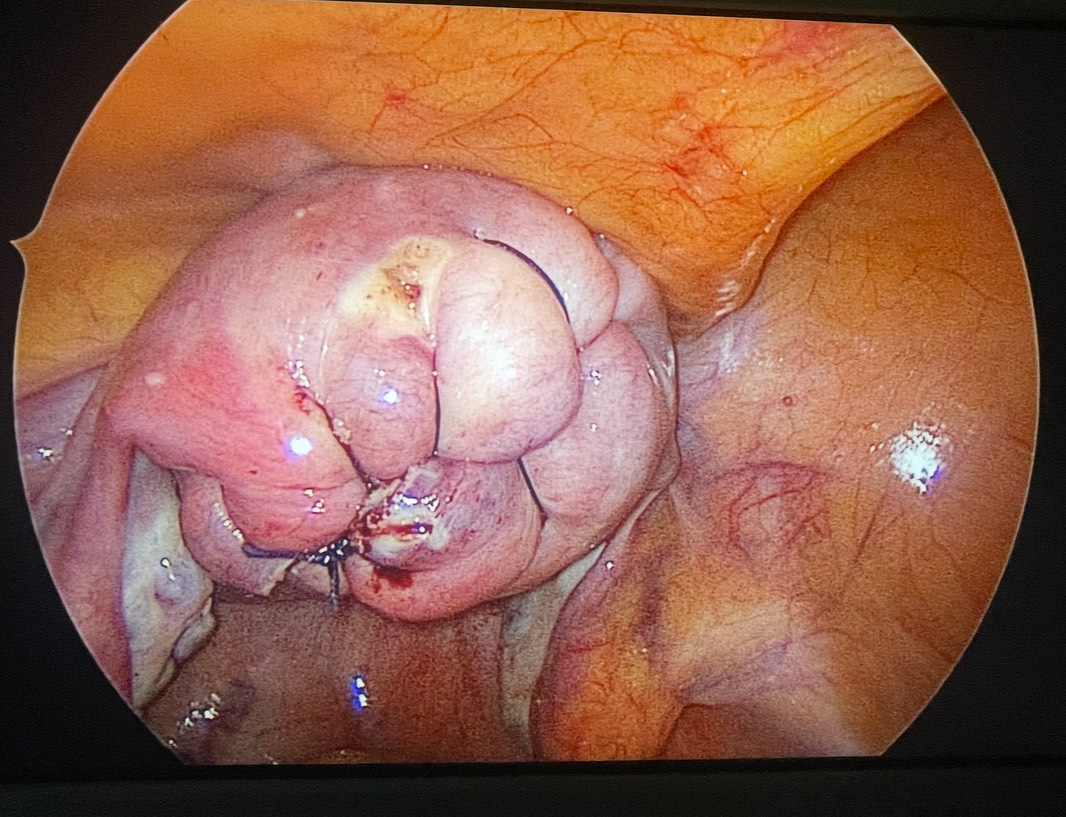

110 Fibroids Removed

110 Fibroids Removed - Saving Uterus for Future Childbirth

110 Fibroids Removed - Young Patient